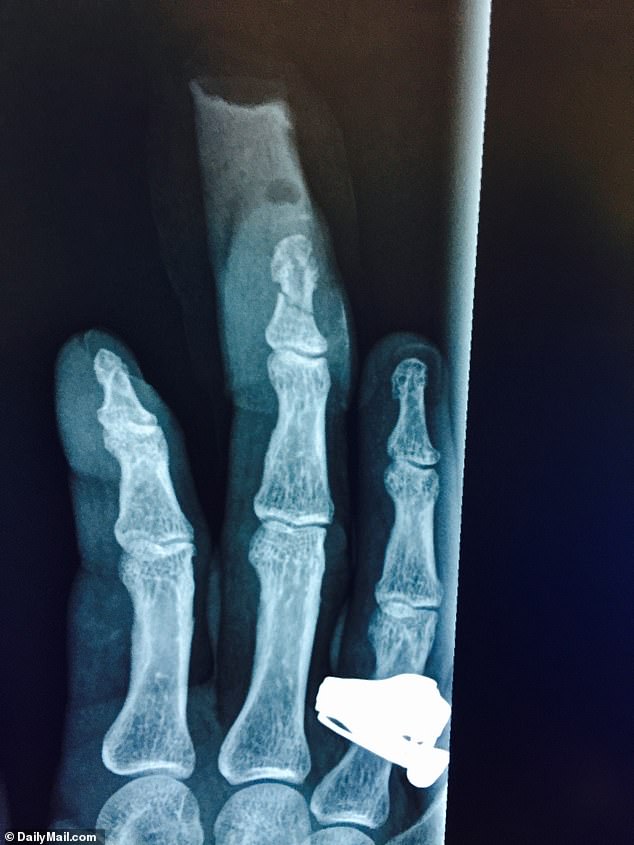

D61 v01 | D61 v02 | D61 v03 | X-Rays |

| | | |

graphic, so links only for the following 3 pics of JD's finger: